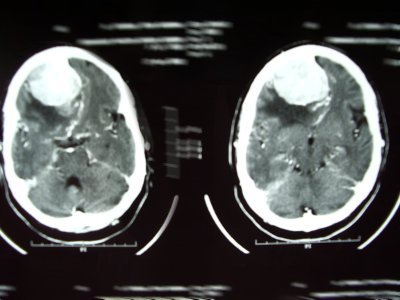

Tumores cerebrales